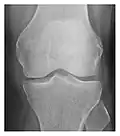

Occult osseous injuries may result from a direct blow to the bone by compressive forces of adjacent bones against one another or by traction forces during an avulsion injury. Lesions in the tibial plateau, hip, ankle, and wrist are often missed. In a tibial plateau fracture, any disruption of the posterior and anterior cortical rims of the plateau should be sought. Impaction of subchondral bone will appear as an increased sclerosis of the subchondral bone (Figure 1). In the hip, posterior acetabular fractures also present subtle radiographic findings. The acetabular lines should then be carefully examined keeping in mind that the posterior rim, which is harder to see on X-rays, is more frequently fractured than the anterior rim (Figure 2). In the wrist, detection of carpal bone fractures is often challenging, with up to 18% of scaphoid fractures radiographically occult. Carpal fractures, especially the scaphoid, are associated with the risk of avascular necrosis. In apparently normal wrist radiographs from symptomatic patients, if there is history of a fall on an outstretched hand with pain in the anatomic snuffbox, suggesting scaphoid injury, the initial examination with posteroanterior, lateral, and pronation oblique views must be complemented by other specific views such as supination oblique and the "scaphoid" view A careful examination of cortices for evidence of discontinuity or offset and cancellous bone for lucency is necessary (Figure 3).[1]

Figure 3: A 26-year-old man presenting with wrist pain after being assaulted. (a) Initial anteroposterior radiograph shows a subtle linear lucency within the scaphoid extending to the scaphocapitate articular surface that was overlooked (arrow). (b) Initial "scaphoid" view was negative. (c) Followup anteroposterior radiographs, 12 days later, shows obvious scaphoid fracture (arrows).[1]